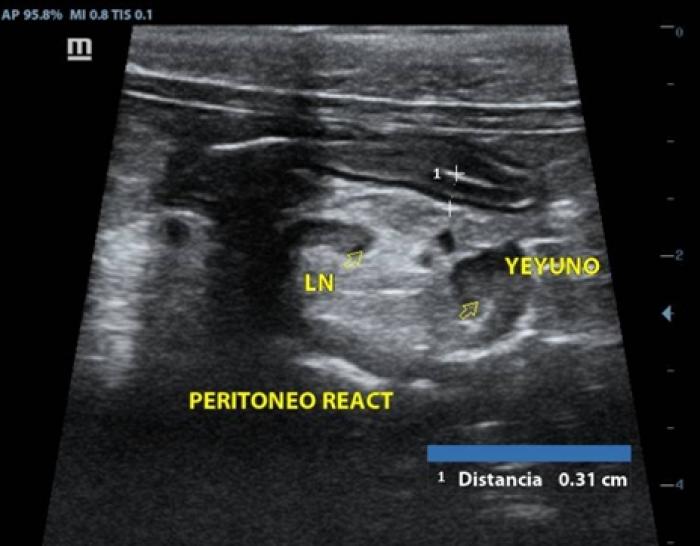

Química sanguínea: urea disminuida (5.6 mmol/l),los demás analitos dentro de rangos normales, hemograma sin alteraciones. Ultrasonido abdominal con ayuno de 8 h en el cual se observó estómago con presencia de gas, engrosamiento de segmentos duodenal (0.39 cm) (Figura10)y yeyunal (0.30-0.31 cm), el yeyuno con pérdida de definición de capas, así como la presencia de linfonodos yeyunales reactivos, con grasa perinodal hiperecoica y peritoneo reactivo adyacente al yeyuno (Figura11),vesícula biliar con presencia de sedimento biliar en cantidad moderada.

Los signos clínicos, así como los hallazgos que suelen observarse en el ultrasonido abdominal tales como aumento en el grosor de las capas intestinales, pérdida de definición de las capas, linfadenopatía reactiva y peritoneo hiperecoico son comunes para ambas enfermedades, por lo que en ningún caso se debe emitir un diagnóstico por este método ni basado en signología clínica. El promedio de las mediciones de la pared intestinal de ambos gatos superaron los 0.28 cm, por lo cual se justificaron la toma de las biopsias. La prueba gold standard para la diferenciación de las enteropatías crónicas felinas es el examen histopatológico de muestras de biopsias teñidas con H&E5.